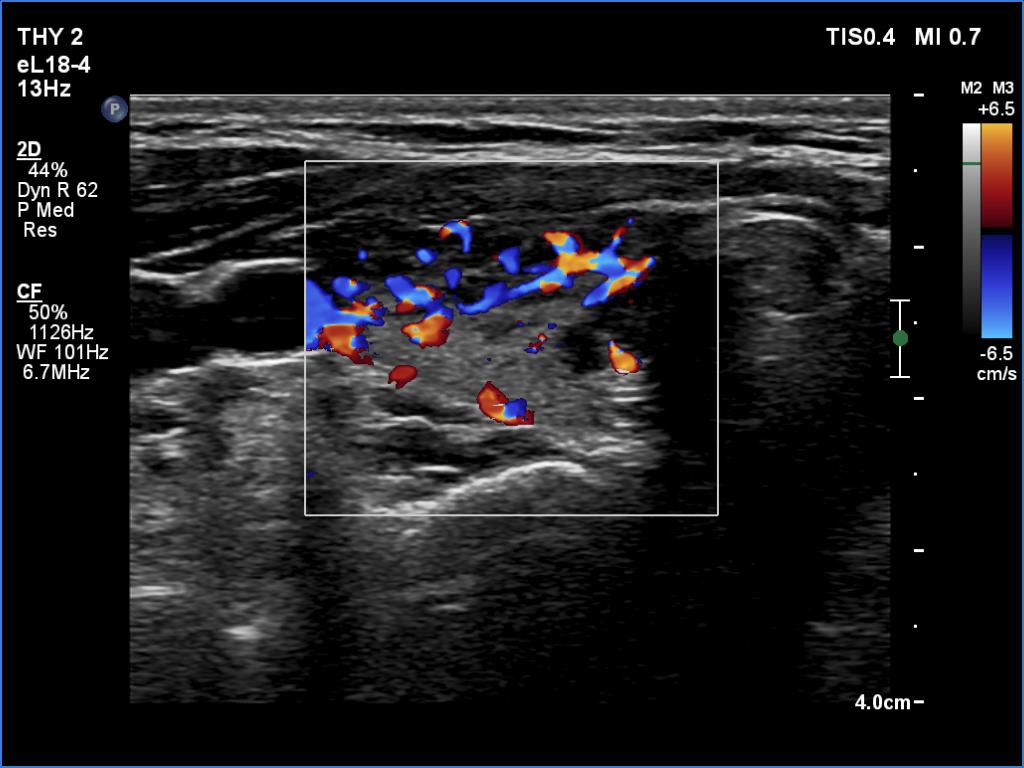

First examination (first row of images):

Clinical data: A 26-year-old woman at the 8th gestational week was referred for evaluation. She has been treated for hypothyroidism for 5 years.

Palpation: Both lobes were firm on palpation. No nodule could be palpated.

Laboratory tests: TSH 6.24 mIU/L, FT4 10.1 pM/L on daily 50 microgram levothyroxine.

Ultrasonography. The thyroid was echonormal and presented numerous hypoechogenic discrete areas. The echogenicity index was around 30% and 60%, right and left lobe, respectively. None of the discrete areas corresponded to pathological nodule.

Suggestion: to increase the dose of levothyroxine to daily 75 micrograms. Repeat TSH in 6 weeks.